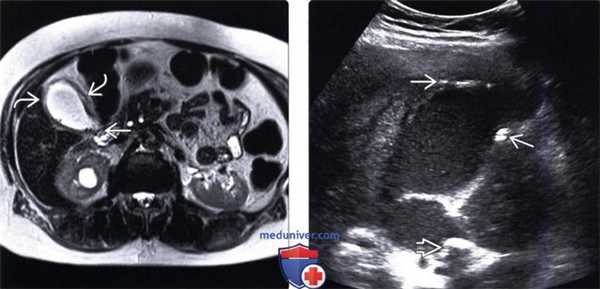

МРТ живота. Гипоинтенсивные конкременты в желчном пузыре на фоне умеренно выраженного отека перихолецистических тканей

(Левый) МРТ в режиме Т2 HASTE. На аксиальном срезе у пациента с острым кальку-лезным холециститом визуализируются множественные мелкие конкременты и интрамуральный отек.

(Правый) На продольном косом УЗ срезе у пациента с острым эмфизематозным холециститом видны растянутый заполненный сладжем желчный пузырь и вколоченный конкремент. Источником ярких интрамуральных эхосигналов является газ.